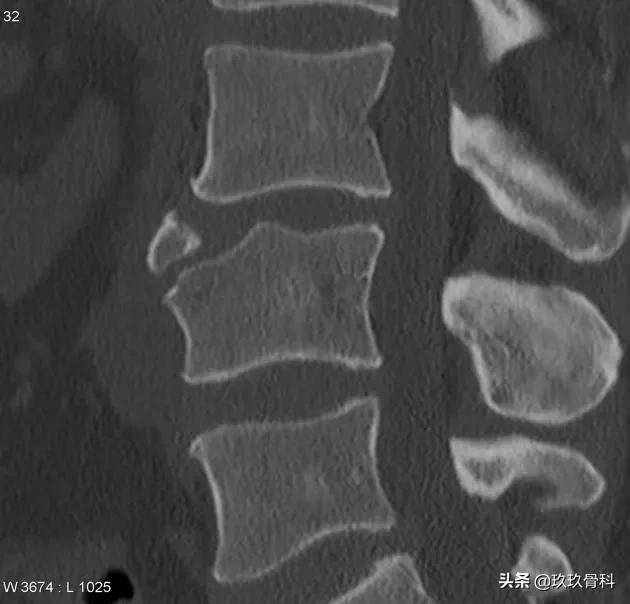

年轻患者,腰背痛就诊。CT影像可见椎体前上缘局灶性骨质缺损,可见一游离类三角形骨性密度影。

CT显示 椎体前部局限性骨质缺损,游离骨块位于缺损区前方,边缘硬化,周围无软组织改变,有时缺损区见软组织密度影,为邻近突出的椎间盘。